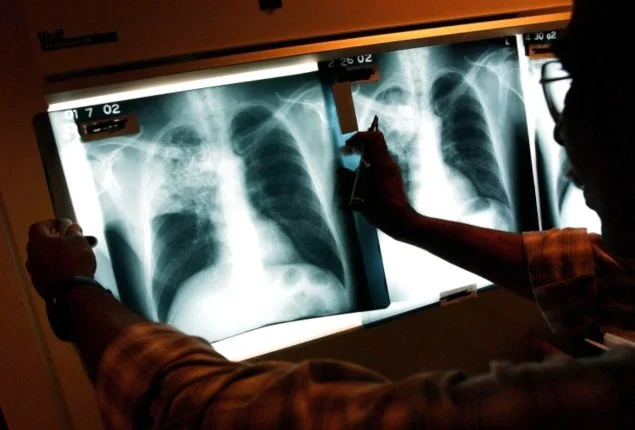

ISLAMABAD: The World Health Organization (WHO) has officially classified Pakistan as one of the top five high-burden countries for tuberculosis (TB), reporting record-high cases in 2023.

Alongside India, Indonesia, China, and the Philippines, Pakistan accounted for more than half of the 10.8 million TB cases reported globally, highlighting a persistent public health crisis despite the existence of treatment and prevention measures.

In its Global Tuberculosis Report 2024, the WHO indicated that newly diagnosed TB cases surged to 8.2 million in 2023, a notable increase from 7.5 million in 2022, marking the highest number of cases since global monitoring began in 1995.

While TB-related deaths showed a slight decline from 1.32 million in 2022, the disease continues to proliferate, particularly in resource-limited environments where factors like undernutrition, diabetes, smoking, and HIV infection are prevalent. Alarmingly, nearly 56% of the global TB burden in 2023 was concentrated in Pakistan and its neighboring high-burden countries.